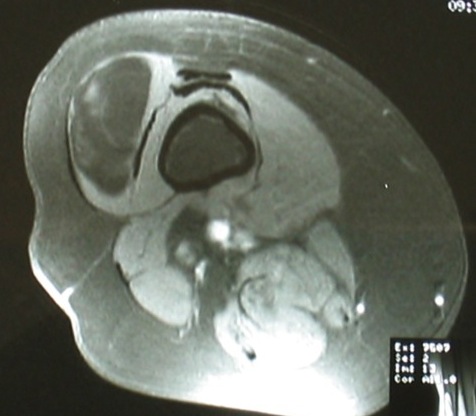

MRI

Same signal intensity as surrounding fat

Intra-muscular lipoma